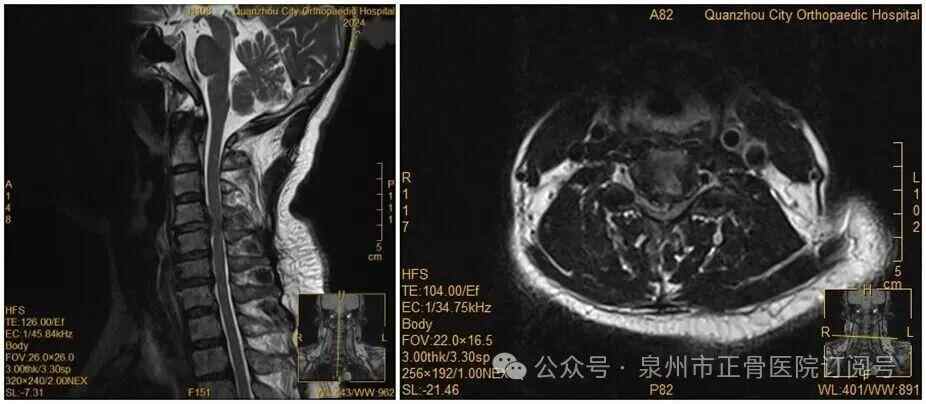

此前,她因手麻、酸痛到医院就诊,被查出颈椎间盘突出症罗瑟汉姆 vs 保顿艾尔宾 。脊柱二科杨声坪主治医师回忆:“会诊时我们明确告知患者,她的颈椎间盘已经巨大脱出,符合手术指征,建议尽快手术。但她坚持想保守治疗。”

没想到,会诊当晚,王女士翻身拿手机的瞬间,双手突然失去知觉——关键肌肌力降至1级或0级,确诊为瘫痪罗瑟汉姆 vs 保顿艾尔宾 。“推测是翻身时,脱出的椎间盘突然进一步卡压到脊髓神经,引发了急性症状。”医生表示。

王女士术前MRI